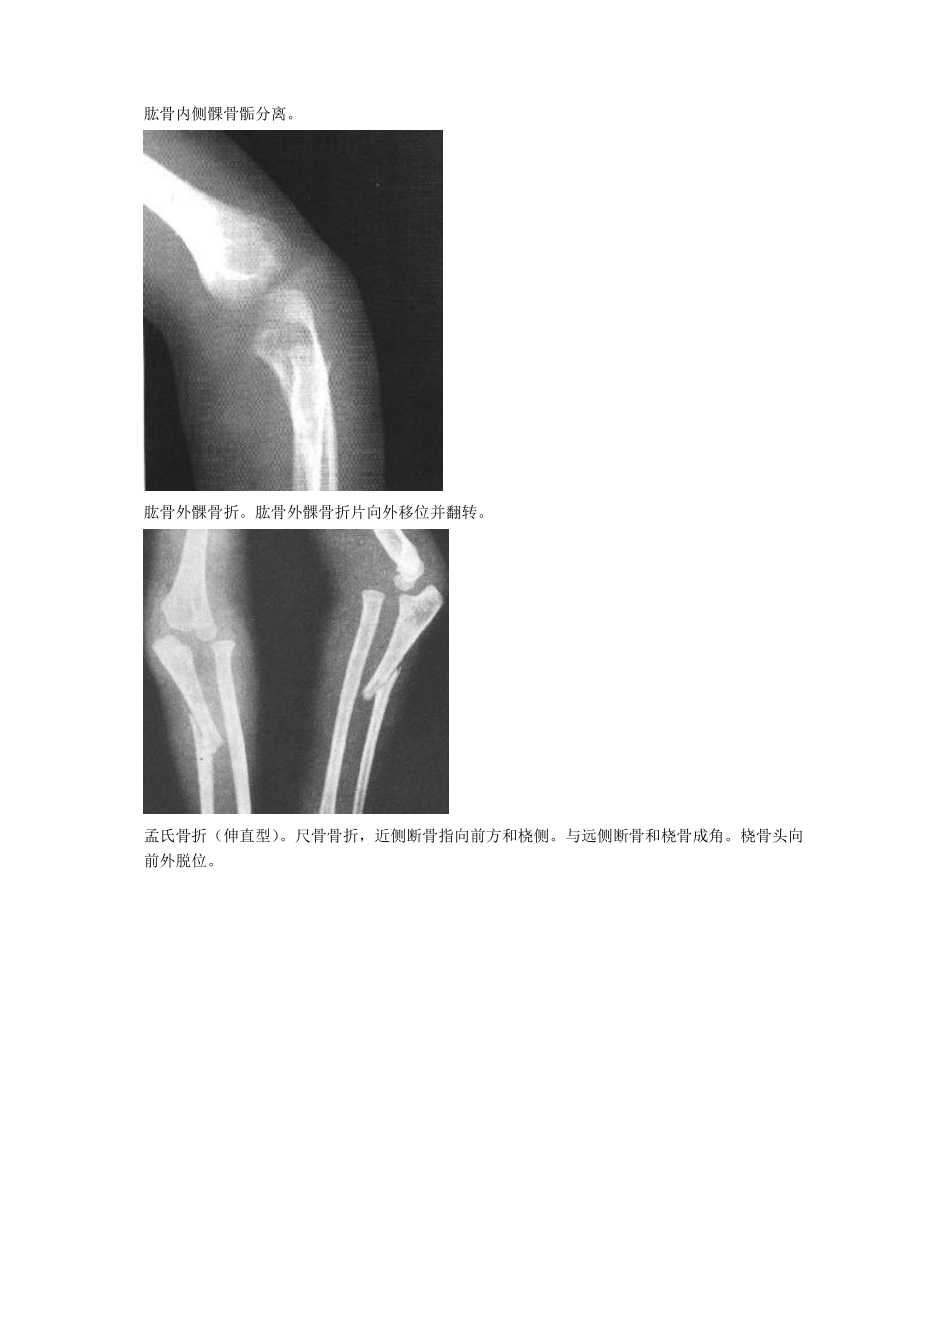

骨折图片大全!请进锁骨骨折。锁骨骨干中段横断骨折。断端向上移位,形成凸向上之成角畸形。肩胛骨粉碎性骨折。肩胛骨外缘见一垂直形骨折线,上缘尚见星芒状骨折线。肱骨外科颈骨折(外展型)。肱骨骨干骨折。远侧断骨向上外方移位,附近有小碎骨片。肱骨髁上骨折。骨折线呈不规则横形,远端骨片稍向掌侧移位。肱骨内侧髁骨骺分离。肱骨外髁骨折。肱骨外髁骨折片向外移位并翻转。孟氏骨折(伸直型)。尺骨骨折,近侧断骨指向前方和桡侧。与远侧断骨和桡骨成角。桡骨头向前外脱位。盖氏骨折。桡骨中下1/3骨折,伴远端尺桡关节脱位和尺骨茎突骨折。柯雷氏骨折。桡骨下端横形骨折,远端断骨向背侧倾斜移位,侧位片呈“匙”样畸形,伴尺骨茎突骨折。史密斯骨折。腕舟骨骨折。腕舟骨中部可见透亮线。第一掌骨基底部骨折。下肢骨折图片股骨颈骨折腓骨下段螺旋形骨折并踝关节半脱位胫骨下段斜形骨折尾指近-中节骨粉碎性骨折并完全性脱位跟骨骨折图片